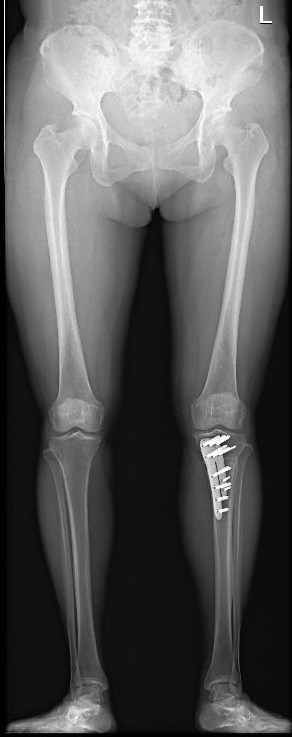

图7 膝骨关节炎全膝关节表面置换术a术前

图7 膝骨关节炎全膝关节表面置换术b术后

图7 :a图示双膝骨关节炎严重、外翻畸形。b图示右侧全膝关节表面置换术后